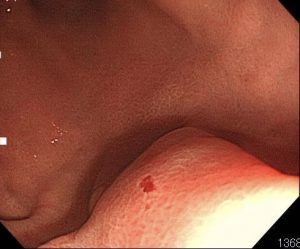

1匹目です。胃の前庭部(奥の方)に食いついています。